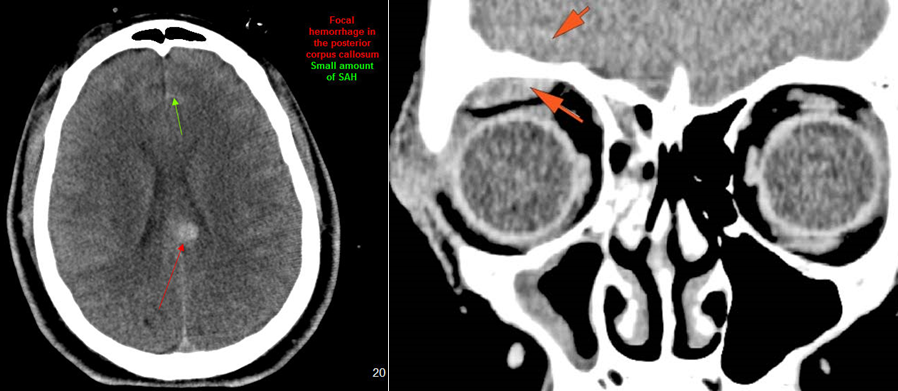

Intracranial

There is subperiosteal, epidural or subdural hematoma and/or pneumocephalus along the boney walls of the anterior or middle cranial fossa or elsewhere.

There is evidence of parenchymal brain injury .